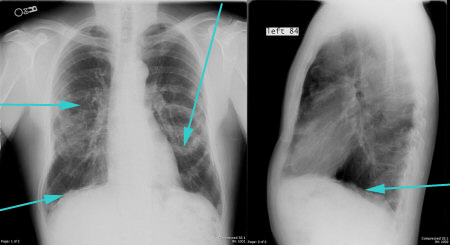

- рентген легких в двух проекциях: фронтальной и боковой;

На рентгенографии симптомы выпотного плеврита легких отображаются как интенсивное однородное затемнение в нижних долях органа. Высокое стояние диафрагмы наблюдается при небольшом скоплении жидкости. Средостение смещено к здоровому легкому. При выполнении снимка в латеропозиции (больной ложится на бок) происходит горизонтальное смещение экссудата.

При перкуссии отмечается ослабление перкуторного звука, причем верхняя граница представляет собой косую линию-Дамуазо, которая хороша видна на рентгенографии. При выслушивании легких фонендоскопом отчетливо слышен шум трения плевры, он похож на скрип снега. Дыхание в местах скопления жидкости резко ослаблено.